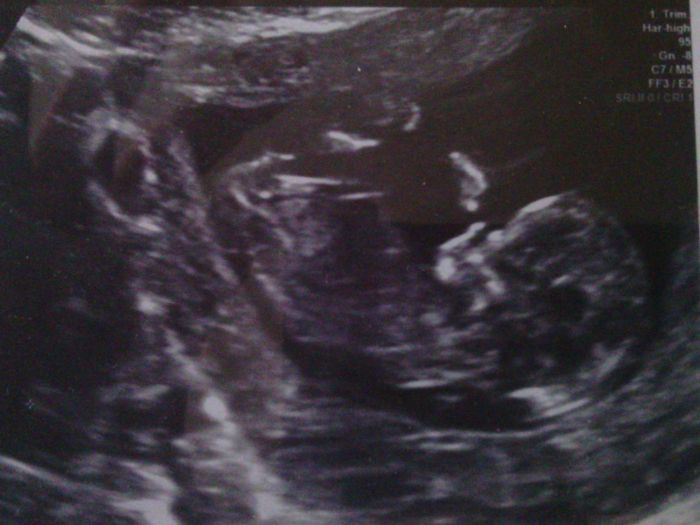

Ahoj holky, tak to dneska klaplo, jsem šťastná. Screening dopadl dobře, vše je v naprostém pořádku a za 14 dní se dozvím jak dopadla krev, pokud se jim něco nebude líbit tak se ozvou. Jinak mně vše ukázal i jak mám plný nacpaný žaludeček, to jsem teda koukala, nebude to zatím žádný divoch,jen trošičku se tam hýbal, ale moc tomu nedal. Jsem dnes 12+1 a měříme 5,53cm. Přikládám fotečky.